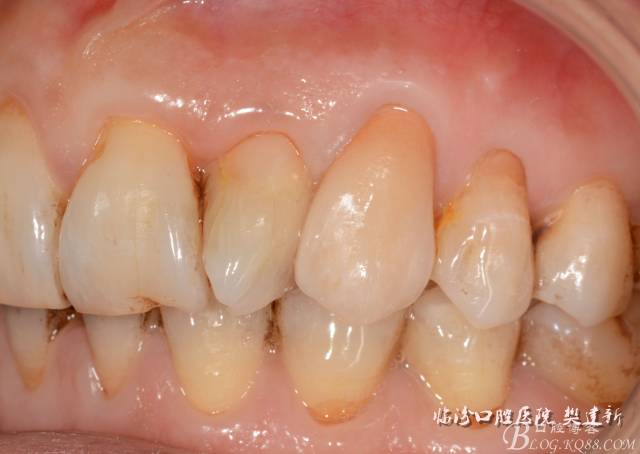

圖1  23口內(nèi)修復(fù)前情況:殘根位于齦上3MM,牙周無紅腫.

640.jpg